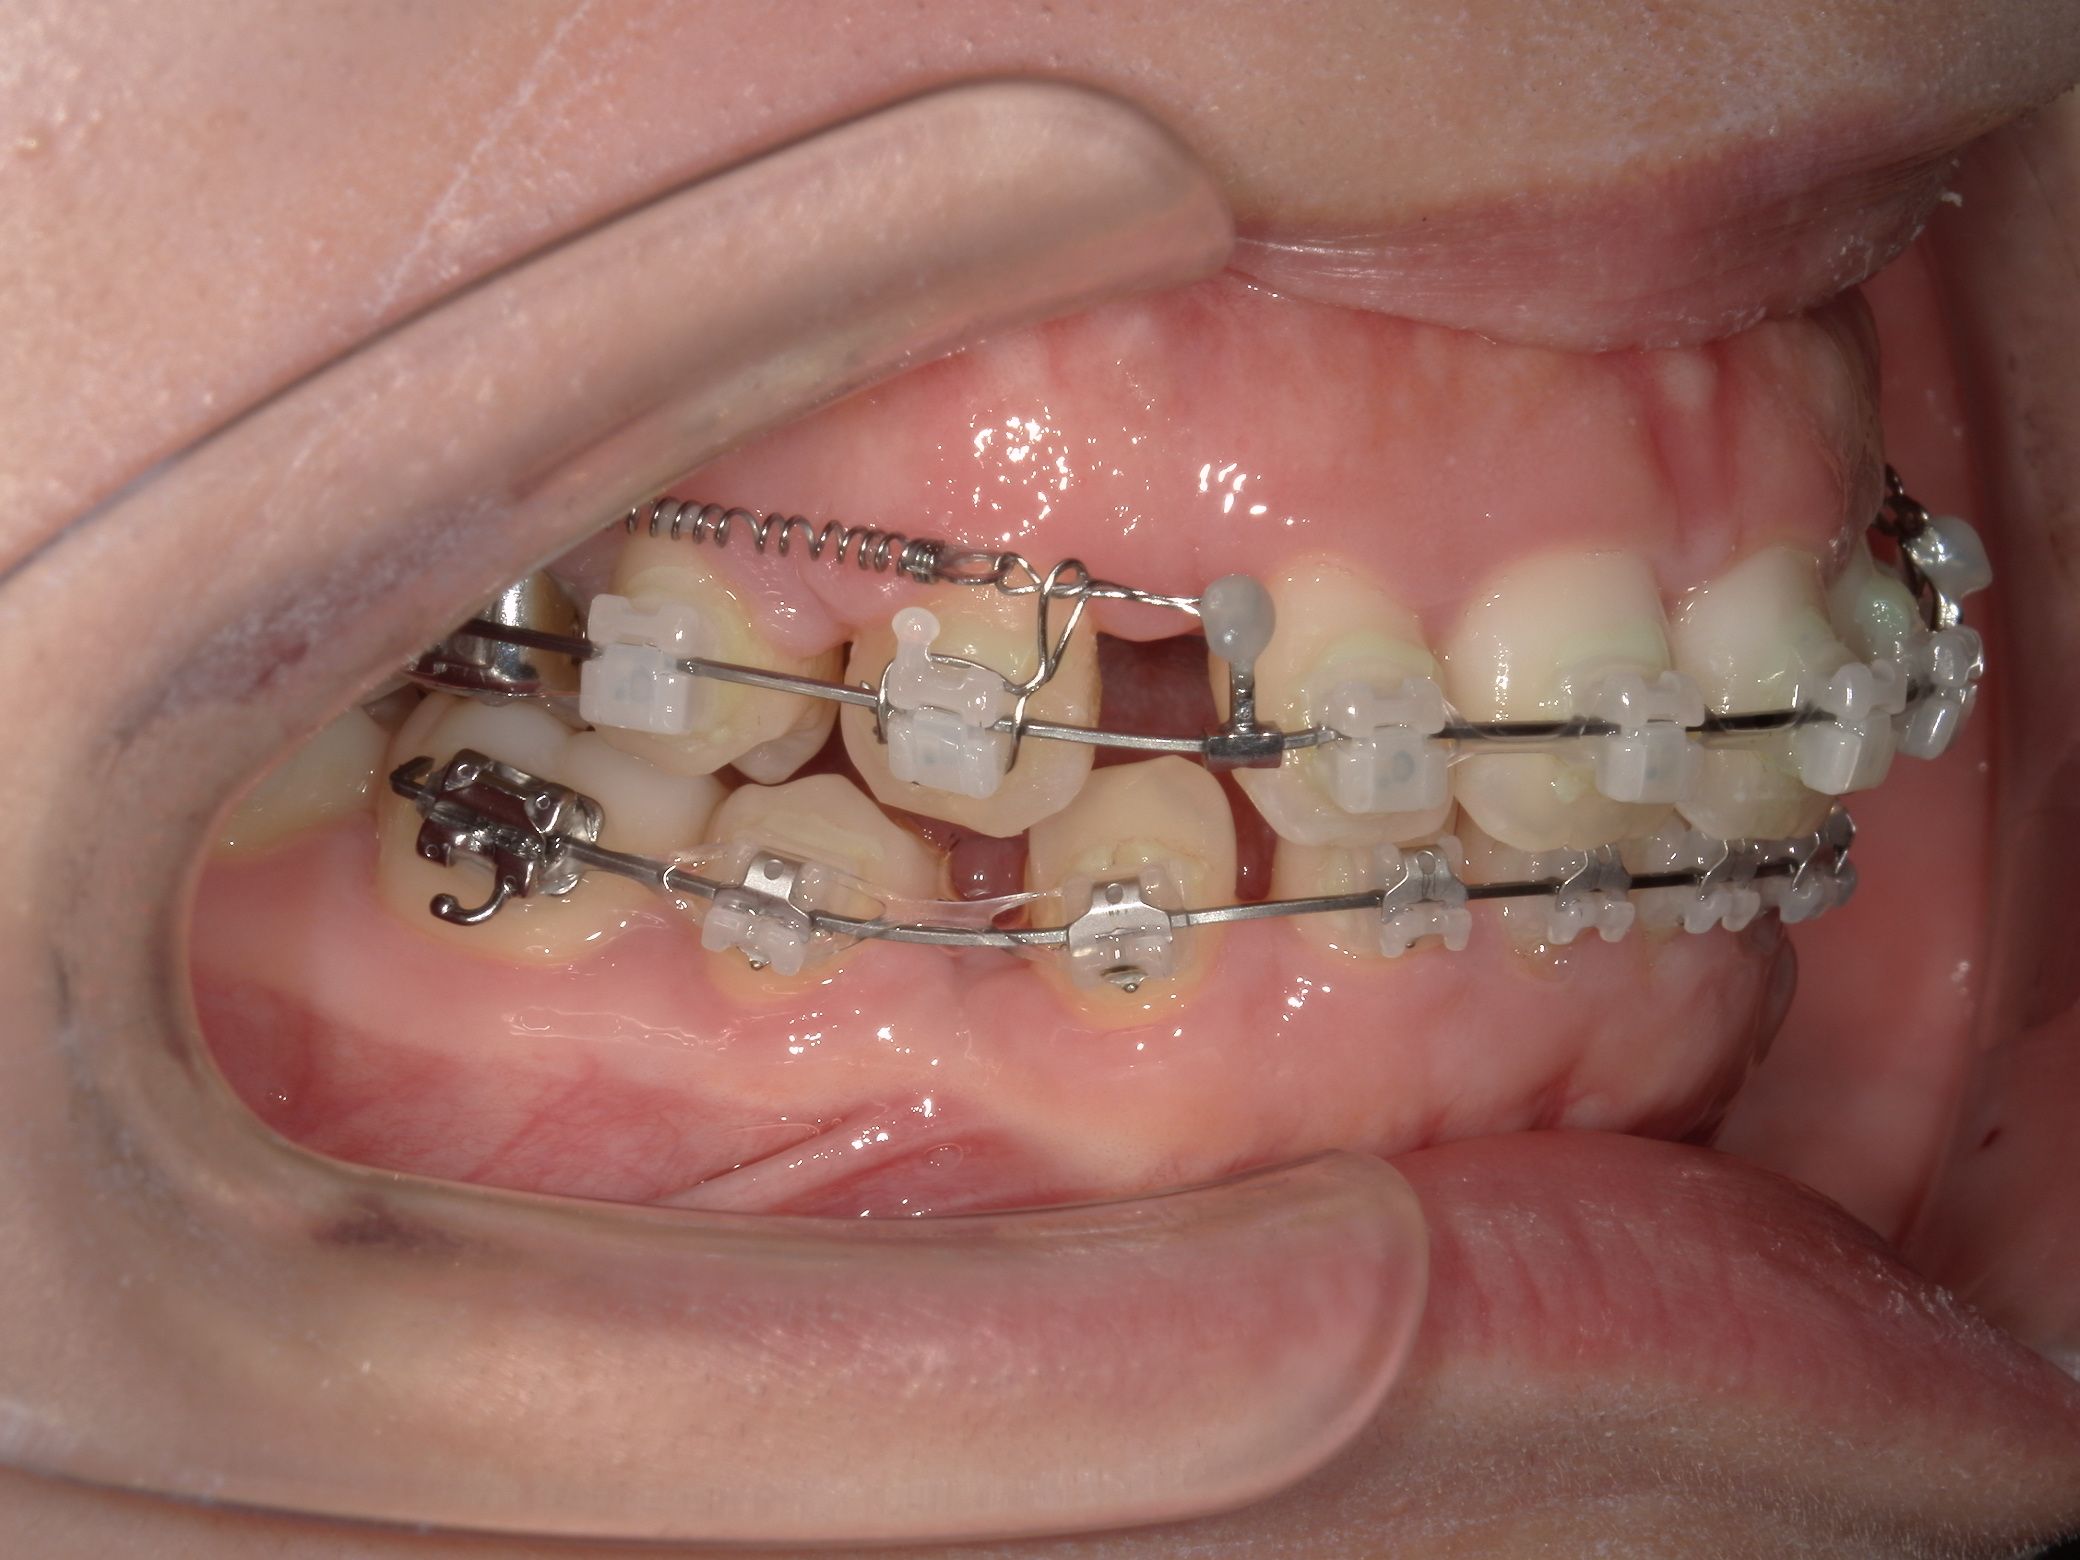

リカバリー症例1

他院の非抜歯矯正後、当院で再治療したケース

リカバリー症例の初診時の口腔内|奈良の矯正歯科

初診時

抜歯矯正1年後の口腔内|奈良の矯正歯科

治療1年後

抜歯矯正完了後の口腔内|奈良の矯正歯科

治療完了

他院で非抜歯矯正を受け、歯並びは改善したものの、口元の突出感が残ったまま治療が終了。当院で精密検査を行った結果、上下4本の抜歯によるリカバリー治療が必要と判断しました。